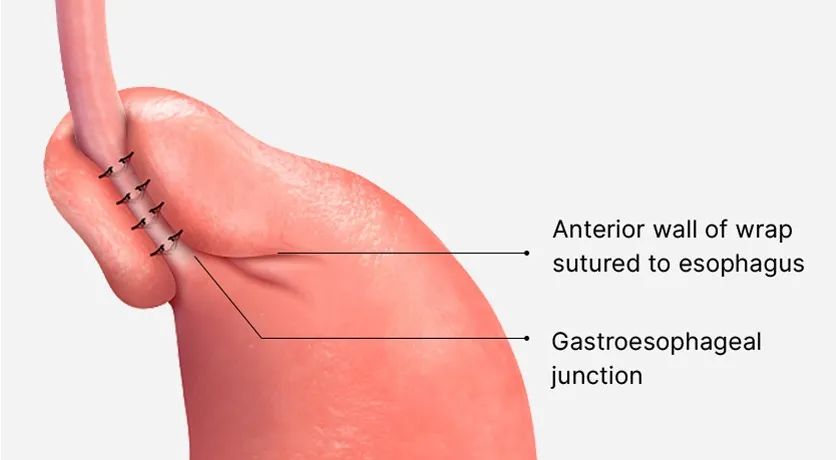

4.胃底折叠术。

将胃底包裹在下段食管周围,并用缝线将其固定,收紧分隔两个器官(下食管括约肌)的肌肉。

Nissen胃底折叠术

该手术包括收缩下食管括约肌,通过覆盖下食管外部周围的胃顶部来防止反流。Nissen 将该手术描述为围绕食管下端进行 4-5 厘米距离的 360 度胃底折叠术。虽然它可以很好地控制反流,但它与导致吞咽困难和胀气综合征的心脏部分功能过度相关。在胀气综合症中,胃中充满空气,因为胃的心脏部分功能过度,无法打嗝。患者饭后感到饱胀并排出过多的肠胃气。

部分胃底折叠术

部分胃底折叠术是为了避免贲门部分过度功能而进行的,涉及食管远端4cm周围的270度胃底折叠术。部分胃底折叠术可以在后侧(Toupet)或前侧(Watson)进行。与全胃底折叠术相比,它的副作用较少,但失败率较高。